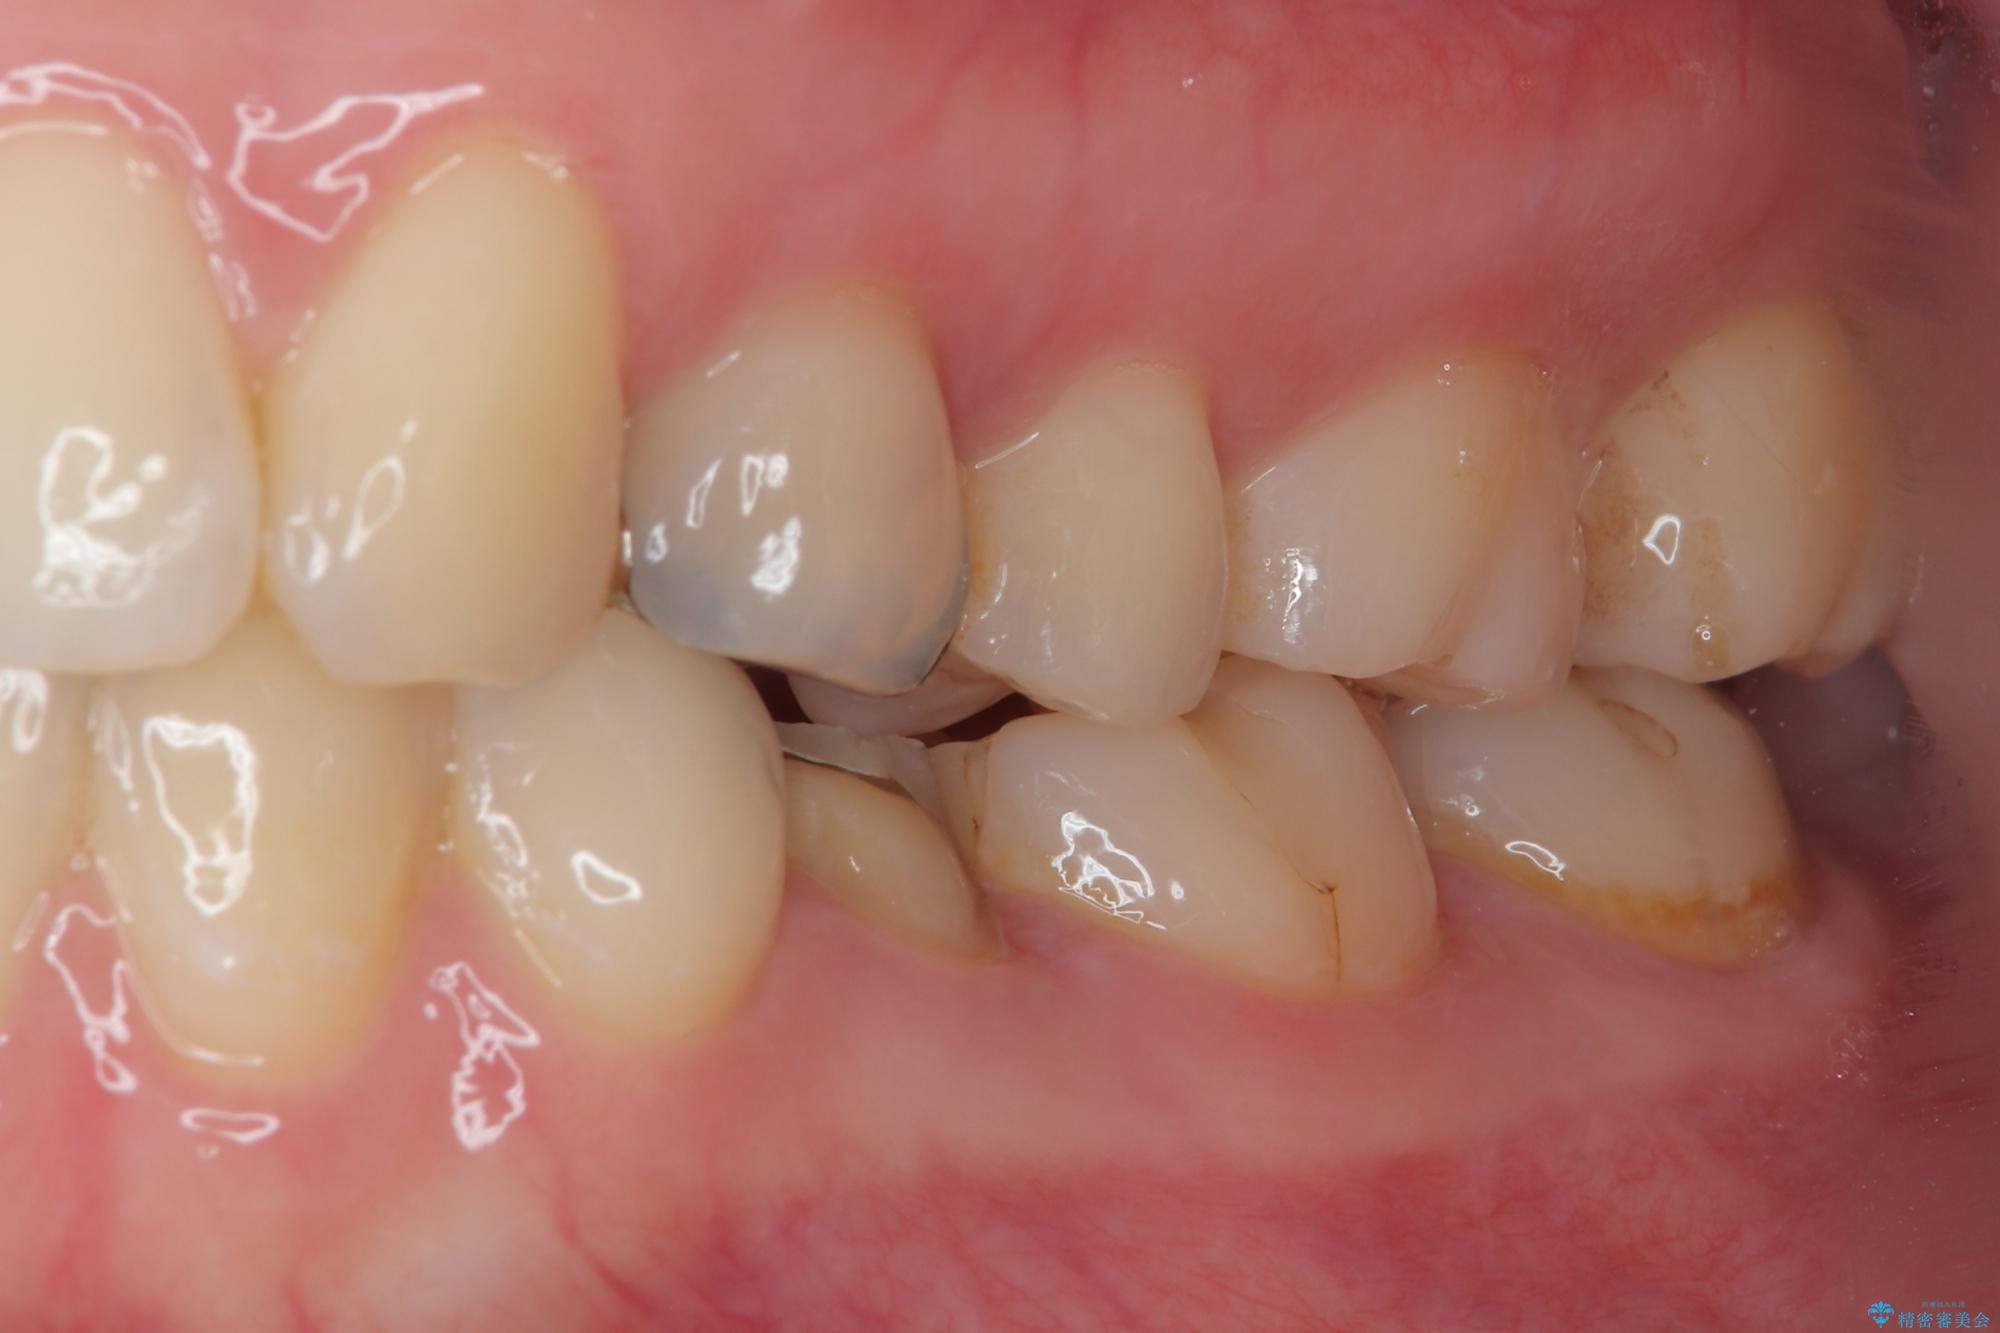

適合の良い被せものが入り、審美面も気に入っていただけました。被せものが割れていたという経緯もあったため少しだけ被せものの厚みを多めに確保してあります。

当院で矯正治療も行っているため、今後もリテーナーを使ってもらいながら経過を観察していきます。